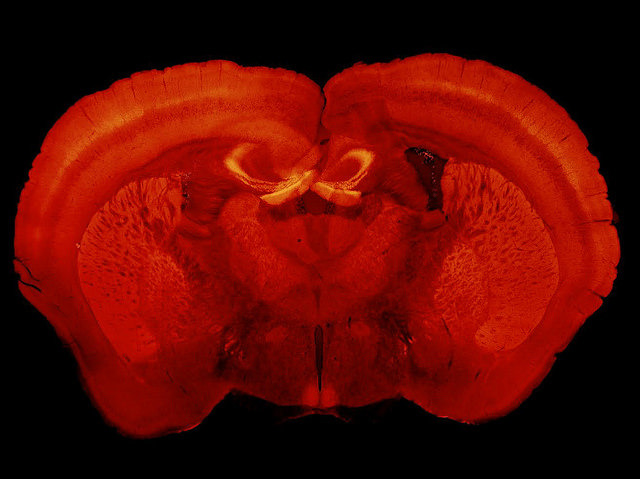

Biological Clock

Jobs with unsocial working hours should come with a serious health warning as nightshift workers face statistically higher risks of heart disease, diabetes, depression, and sleeping difficulties. Humans aren’t nocturnal and disruptions to our circadian rhythm, which regulates the cycle of sleep and wakefulness, can be debilitating. Anyone who’s experienced jetlag will confirm that our stubborn body clocks make us suffer when we try to shoehorn them into new time zones. It’s been known since the 1970s that a part of the brain called the suprachiasmatic nucleus (SCN) – bright spots middle bottom in this cross-section from a mouse – controls our sleep cycle. But what hasn’t been known until now is that the cycle could all be due to a single protein found in the SCN, called neuromedin, that brain cells use to communicate. The discovery gives scientists a new target to aim for when developing future treatments for sleep disorders.